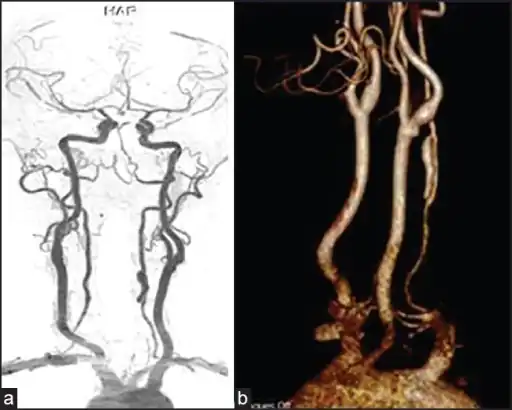

Various diagnostic modalities exist to demonstrate blood flow or absence thereof in the vertebral arteries. The gold standard is cerebral angiography (with or without digital subtraction angiography).[4][14][15] This involves puncture of a large artery (usually the femoral artery) and advancing an intravascular catheter through the aorta towards the vertebral arteries. At that point, radiocontrast is injected and its downstream flow captured on fluoroscopy (continuous X-ray imaging).[16] The vessel may appear stenotic (narrowed, 41–75%), occluded (blocked, 18–49%), or as an aneurysm (area of dilation, 5–13%). The narrowing may be described as "rat's tail" or "string sign".[2] Cerebral angiography is an invasive procedure, and it requires large volumes of radiocontrast that can cause complications such as kidney damage.[16] Angiography also does not directly demonstrate the blood in the vessel wall, as opposed to more modern modalities.[2][3] The only remaining use of angiography is when endovascular treatment is contemplated (see below).[2]

More modern methods involve computed tomography (CT angiography) and magnetic resonance imaging (MR angiography). They use smaller amounts of contrast and are not invasive. CT angiography and MR angiography are more or less equivalent when used to diagnose or exclude vertebral artery dissection.[14] CTA has the advantage of showing certain abnormalities earlier, tends to be available outside office hours, and can be performed rapidly.[2] When MR angiography is used, the best results are achieved in the T1 setting[3] using a protocol known as "fat suppression".[2][3][4] Doppler ultrasound is less useful as it provides little information about the part of the artery close to the skull base and in the vertebral foramina, and any abnormality detected on ultrasound would still require confirmation with CT or MRI.[2][3][4]